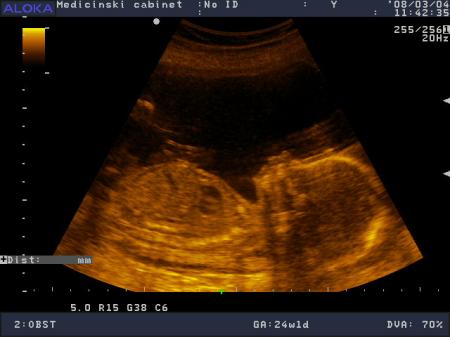

Попросите Вашего врача пропальпировать живот и сказать вам предположительный (и весьма неточный) вес ребенка. Более точно (хотя порой тоже ошибочно) весо-габаритные показатели может вам сказать УЗи-обследование.